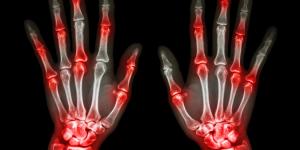

El dolor articular causado por la artritis reumatoide resulta muy molesto y, en algunos casos, impide realizar actividades cotidianas con normalidad. Es por ello que resulta fundamental acudir al médico para que pueda examinar las articulaciones y determinar el mejor tratamiento para reducir los dolores. Sin...